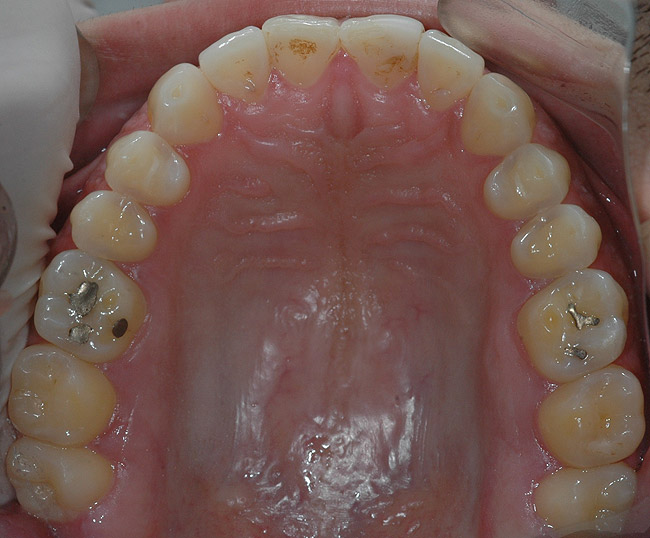

Direct Restorative Treatment of Dental Erosion Caused by

Direct Restorative Treatment of Dental Erosion Caused by Acid Reflux Dentist Define acid reflux and describe the clinical signs and symptoms, identify and explain medications used in the treatment of acid reflux from a patient’s health history, list the. Acid reflux is when the acid from the stomach moves backward into the esophagus, irritating the tissue. How gerd causes tooth erosion. How can your dentist tell if you have acid reflux?. Acid Reflux Dentist.